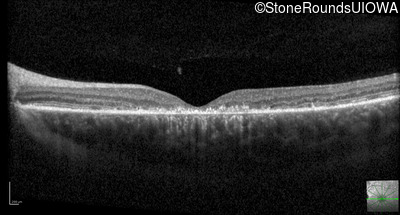

Optical Coherence Tomography - Left - 20/25 +1 sc

Exemplar / OCT Stack